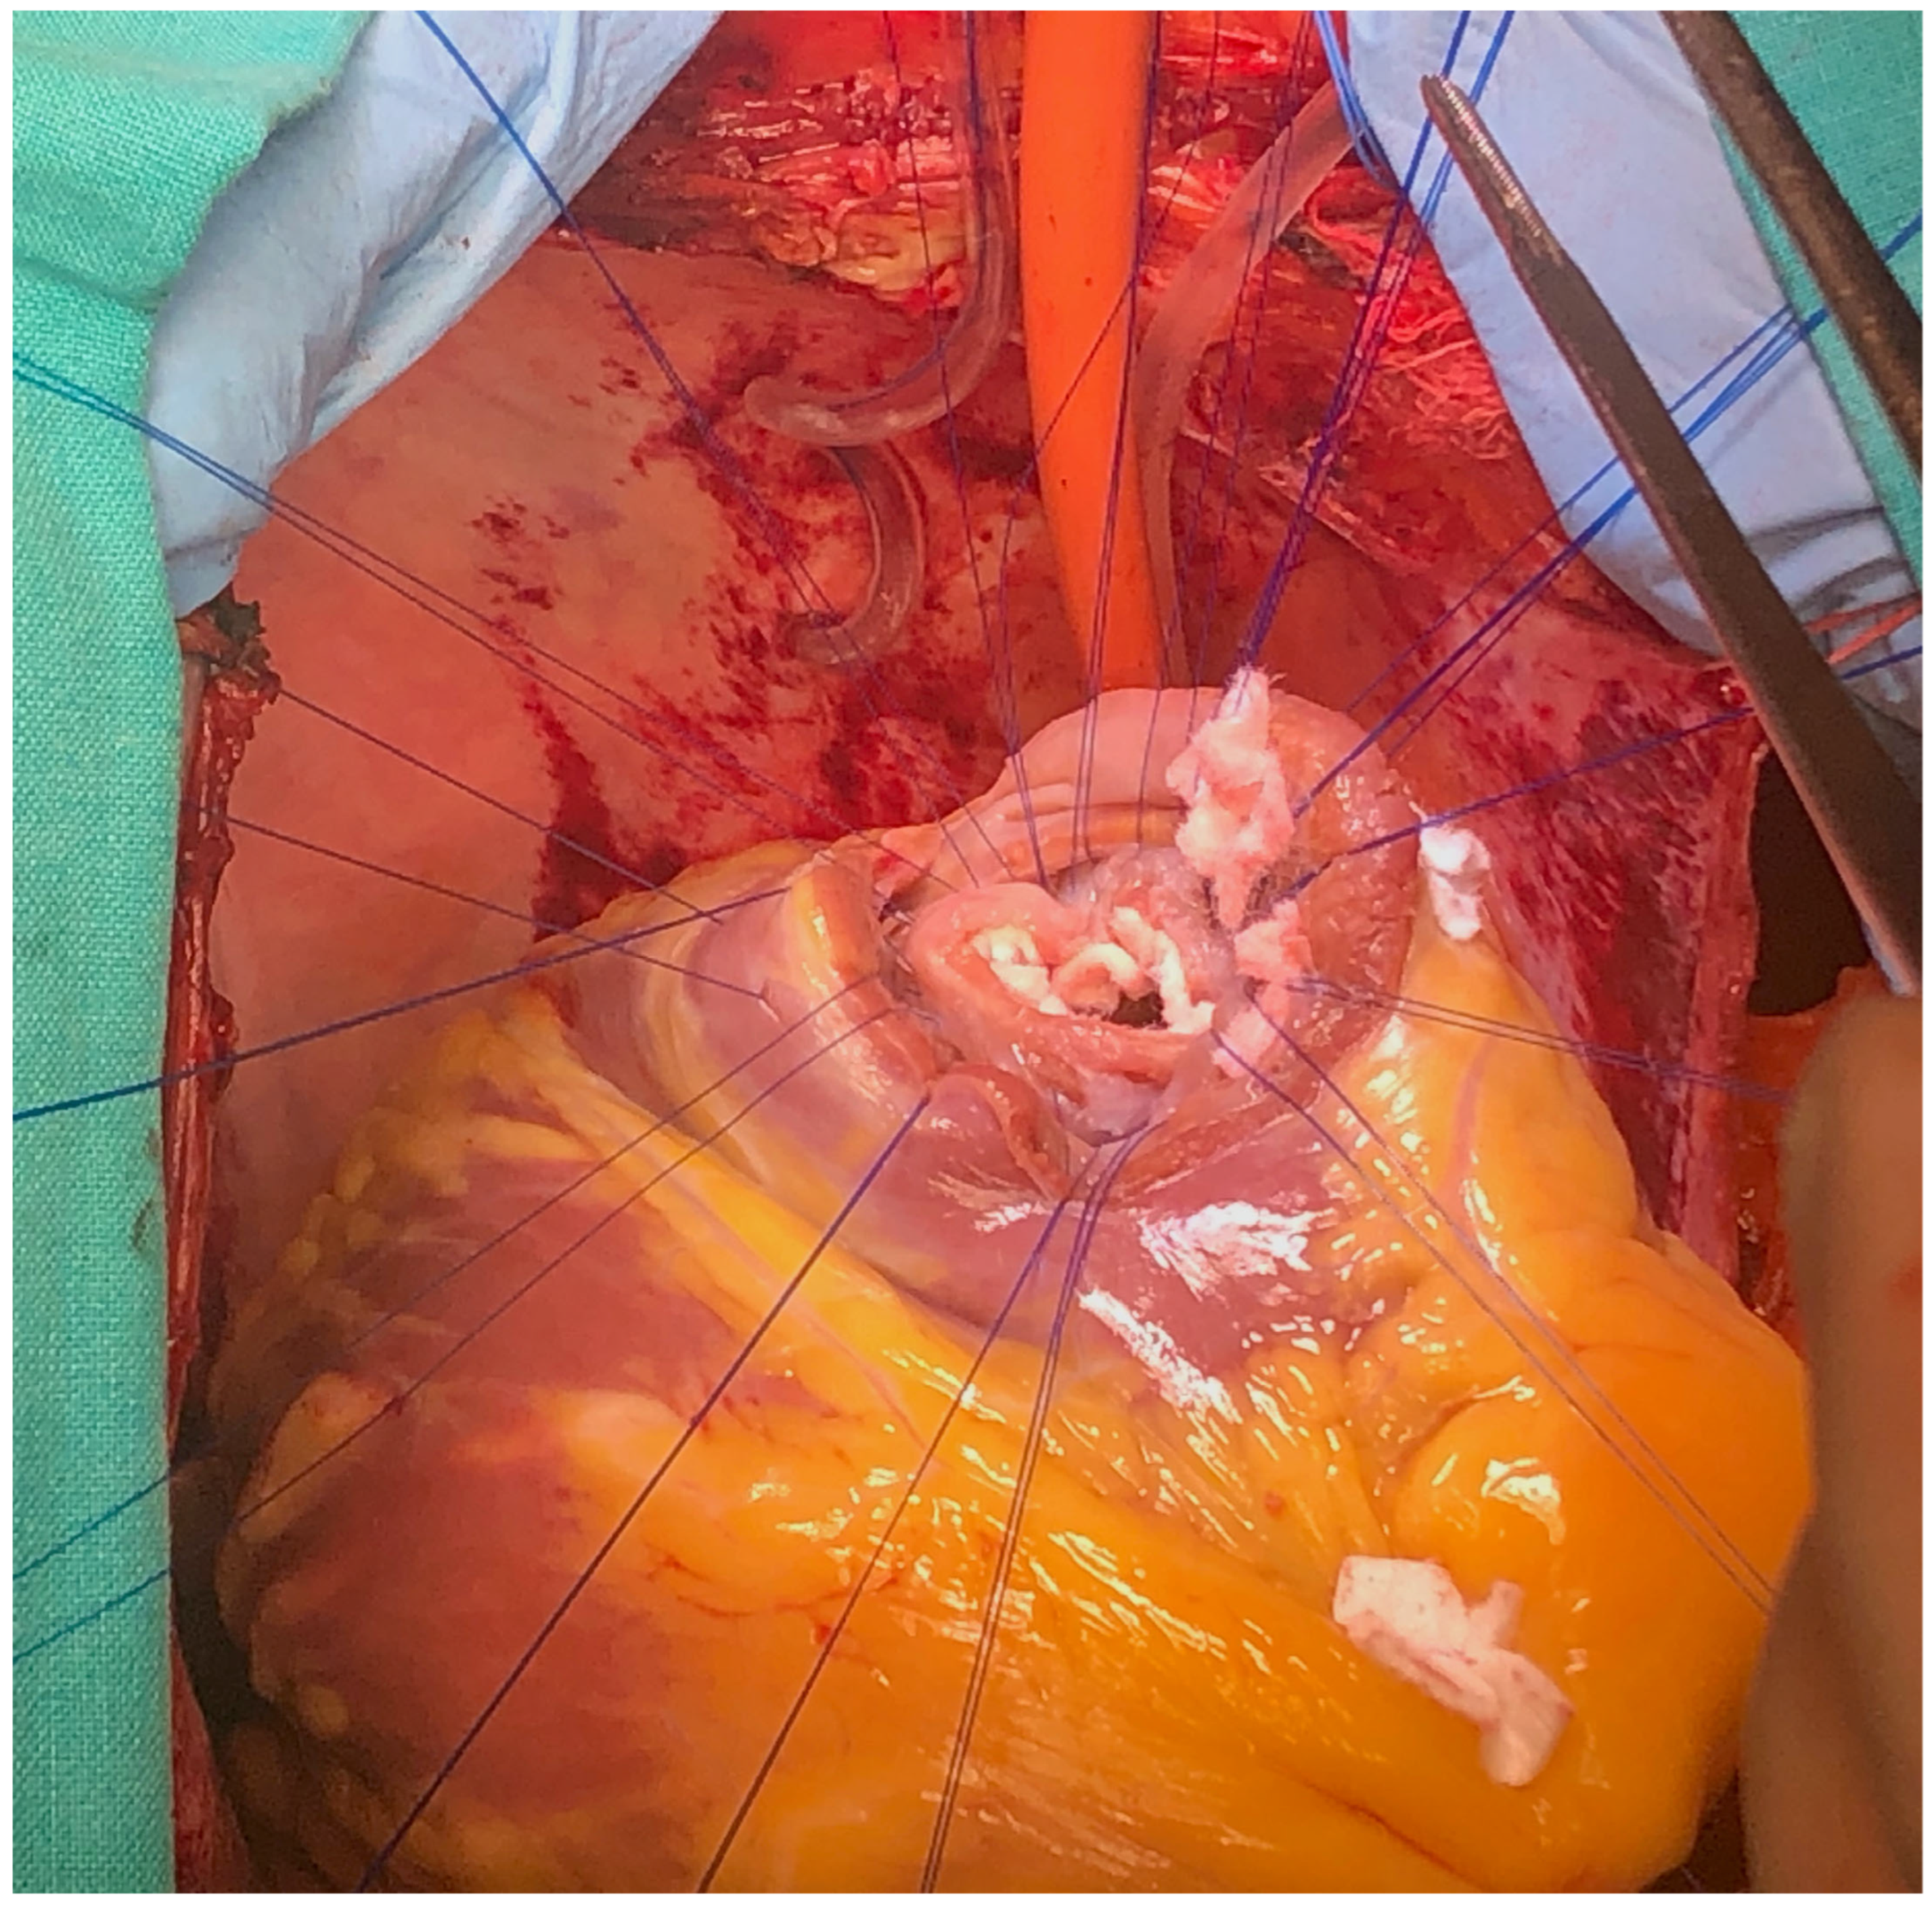

The case was discussed in the multidisciplinary heart team (cardiologist, interventional cardiologist, cardiac surgeon, anesthesiologist) and, after informed consent, it was decided for a watchful waiting tactic, planning a delayed repair. Preoperatively, the patient was evaluated with a transesophageal echocardiography (TEE) for better defect characterization and MR quantification (Figure 3 and Figure 4). Percutaneous defect closure was deemed technically unfeasible due to the anatomy of the defect, which was located at the base of the septum and involved the mitral valve apparatus, while also exhibiting significant mitral valve regurgitation.

The surgery was carried out under general anesthesia, with iv induction and inhaled sevoflurane maintenance and total iv anesthesia during CPB. After median sternotomy, bicaval CPB was started, and the heart was arrested using anterograde and retrograde cold blood cardioplegia. After snaring both venae cava, the heart was enucleated with a 3.0 polypropylene stitch at the apex. A 10 cm incision was made on the posterior surface of the left ventricle, 2 mm parallel to the posterior interventricular artery. The margins of the VSD were identified. Interrupted matrass sutures of 2.0 Tevdek were placed circumferentially around the defect and used to secure a 4 × 7 cm bovine pericardial patch. The posterior papillary muscle was retracted into the sutures, so the mitral valve was replaced with a 27 biological prosthesis with preservation of the sub-valvular apparatus. The left ventriculotomy was closed with a double layer surjet suture, reinforced with Teflon felts. Details with surgical technique are shown in Figure 5, Figure 6, Figure 7 and Figure 8.

Figure 5. Surgical technique detail—exposure of VSD.